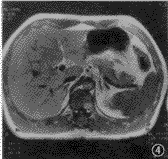

图3,4 患者 男,47岁。肝右叶局灶结节状脂肪浸润,但无占位病变。反相位序列(TR 128 ms,TE 2.7 ms,翻转角70°)示肝右叶低信号结节状脂肪浸润(图3),而在同相位(TR 128 ms,TE 5.3 ms,翻转角70°)上呈等信号(图4)